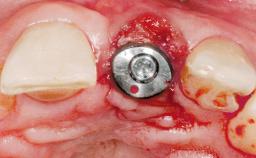

Immediate Flapless Placement of an Implant in a Maxillary Left Central Incisor Site

Pedro Tortamano, Luiz Otávio Alves Camargo

A 42-year-old female patient was referred to our clinic at the School of Dentistry of the University of São Paulo in November 2004, presenting a deficient restoration in the upper left central incisor. The clinical examination revealed no gingival retraction or any signs of gingival inflammation and, therefore, previous periodontal treatment was not considered. The patient presented a high lip line at full smile and a thin tissue biotype. This combination characterized a high-risk situation from an anatomic point of view, which required careful preoperative planning and cautious surgical execution.

Placement Protocol Immediate implant placement

Socket Morphology Single-root socket

Socket Integrity Sufficient, with intact bone walls

Bone Volume Sufficient, with intact walls